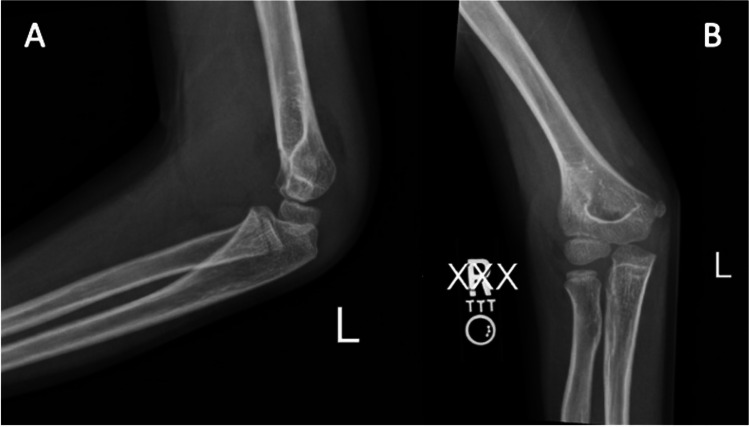

综述目的:本综述旨在全面分析小儿Gartland II型骨折的非手术治疗。最近发现:肱骨髁上骨折(SCF)是儿童人群中最常见的创伤性骨折之一,其特征是肱骨远端内侧柱和外侧柱之间的横向骨折。早期研究强烈反对将闭合复位和铸造作为Gartland II型骨折可接受的治疗方式,因为早期病例系列显示并发症发生率高;然而,最近的研究表明效果更好。Gartland II型髁上骨折的最佳治疗方法尚未完全阐明。本文综述了Gartland II型肱骨髁上骨折非手术治疗的适应症、并发症和结果。此外,它表明需要进一步的研究来指导管理这种情况。

Recent findings: Supracondylar humeral fractures (SCF) are one of the most common traumatic fractures in pediatric populations, characterized as transverse fractures at the distal humerus between the medial and lateral columns. Early studies strongly opposed closed reduction and casting as an acceptable treatment modality for Gartland type II fractures as an early case series showed high rates of complications; however, more recent studies have suggested better outcomes. The optimal management of Gartland Type II supracondylar fractures has yet to be fully elucidated. This review highlights the indications, complications, and outcomes of nonoperative Gartland Type II supracondylar humeral fracture management. Additionally, it demonstrates the need for further research to inform guidelines on managing this condition.